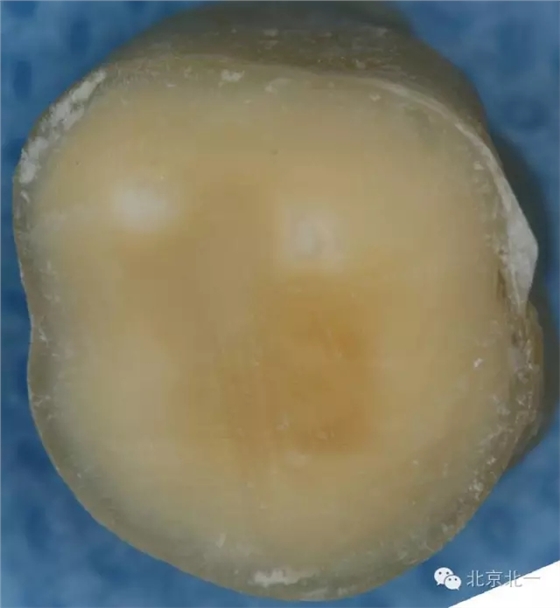

這只是因為學生們對于牙體組織的顏色沒有很好的理解,髓頂?shù)纳珴膳c其下方髓底的顏色有著顯著的不同(下圖為同一顆牙不同層面的片切圖A為髓頂與穿髓孔B為下方的髓底與根管口)。